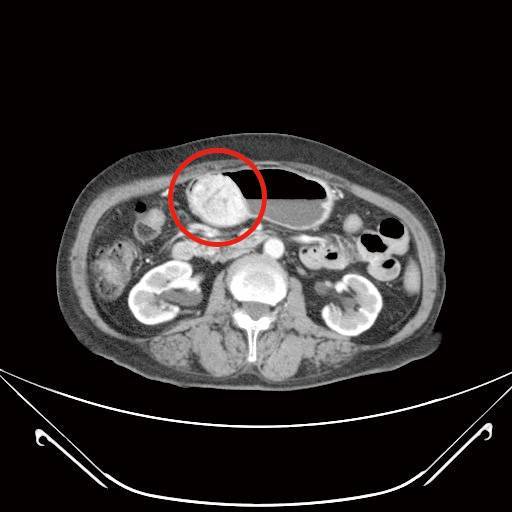

胃腸道基質瘤(上圖)

目前針對胃腸道基質瘤主要的治療方式以手術切除為主,標靶治療為輔。若是經過評估已經有遠端轉移,或腫瘤原發位置屬於手術高度危險區域,或腫瘤太大而無法一次手術完整切除,這些狀況可以先給予標靶治療,這種前導性治療的模式有機會將無法手術的病況轉變成可以手術,而達到更好的治療效果。也因為標靶藥物的介入,整體平均存活率增加3成以上。

手術的目標在於完整將腫瘤切除,以往這類患者需接受超過15公分傷口的剖腹手術(傷口位於腹部正中間),考量病人合併有膽結石問題,故建議接受達文西微創手術,做更細緻的剝離及切除,也可同時處理胃部惡性腫瘤及膽結石,由於術後僅1個3-5公分及3-4個1公分傷口,大幅降低病人術後傷口疼痛感,有助盡早恢復體力與活動力,更快回到日常生活。